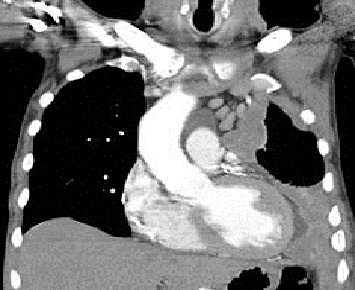

Mesothelioma (or, more precisely, malignant mesothelioma) is a rare form of

cancer that develops from cells of the mesothelium, the protective lining that

covers many of the internal organs of the body. Mesothelioma is most commonly

caused by exposure to asbestos.1 The most common anatomical site for

mesothelioma is the pleura (the outer lining of the lungs and internal chest

wall), but it can also arise in the peritoneum (the lining of the abdominal

cavity), the pericardium (the sac that surrounds the heart),2 or the tunica

vaginalis (a sac that surrounds the testis).

Signs and symptoms of mesothelioma

include shortness of breath due to pleural effusion (fluid between the lung and

the chest wall), chest wall pain and constitutional signs such as unexplained

weight loss. The diagnosis may be suspected based on chest X-ray and CT scan

findings, but must be confirmed either by examining serous effusion cytology or